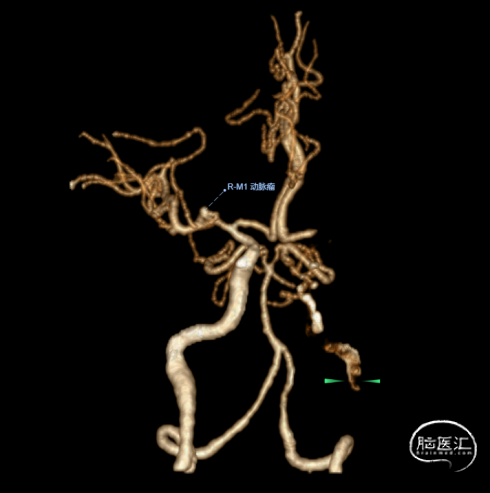

术后24小时复查头颅CT未见出血,CTA提示血管通畅。予加用氯吡格雷单抗抗血小板聚集。